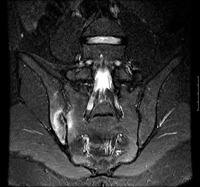

Mais - ressonância nuclear magnética (RNM) do sacro:

edema da medula óssea em uma imagem de recuperação de inversão de tau curto STIR (short-tau inversion recovery) sagital ponderada em T2